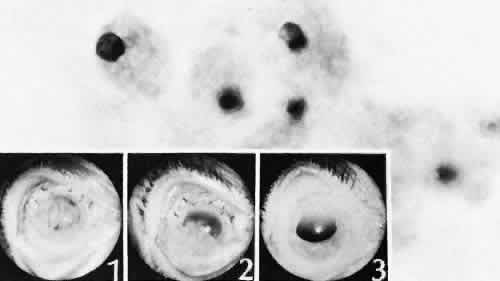

Rupture of the posterior lens capsule (Fig. 28) increases the risk of vitreous loss and limits options for the implantation of an intraocular lens. Retention of lens capsular tissue or vitreous in the wound (Fig. 29) will significantly delay the wound healing process. Vitreous loss leads to an increased incidence of iris prolapse, bullous keratopathy, epithelial downgrowth, stromal overgrowth, wound infection and endophthalmitis, updrawn or misshapen pupil, vitreous bands, postoperative flat anterior chamber, secondary glaucoma, retinal detachment, cystoid macular edema, optic disc edema, vitreousopacities, vitreous hemorrhage, and other sight-threatening consequences.92

Fig. 28. A case of lens capsular rupture during intracapsular cataract extraction. On postoperative day 1 (inset 1), there was considerable retention of lens capsular material nearly obscuring the anterior chamber. By postoperative day 14 (inset 2), considerable clearing of debris has occurred. At 2 months following surgery (inset 3), the anterior chamber was nearly clear. The clearing of the debris was through the action of macrophages ingesting the cortical debris and exiting the eye through the trabecular apparatus. Macrophages filled with lens cortical material from a different case are seen in the main figure. (Periodic acid-Schiff stain; × 700.) (Yanoff M, Scheie HG: Cytology of human lens aspirate. Its relationship to phacolytic glaucoma and phacoanaphylactic endophthalmitis. Arch Ophthalmol 80:166–170, 1968.)